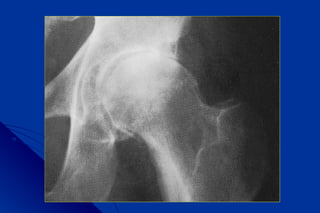

Signes radiologiques communsSignes radiologiques communs

à toutes les coxarthrosesà toutes les coxarthroses

 pincementpincement localisélocalisé dede

l’interlignel’interligne en général supéro-en général supéro-

externeexterne

 OstéophytoseOstéophytose à la périphérie desà la périphérie des

surfaces cartilagineusessurfaces cartilagineuses

 Condensation osseuse sousCondensation osseuse sous

chondralechondrale

 GéodesGéodes

2 - L’analyse des clichés est indispensable pour2 - L’analyse des clichés est indispensable pour

apprécier le caractère primitif ou secondaireapprécier le caractère primitif ou secondaire

Il faut examiner la forme de la tête, mesurer les angles +++Il faut examiner la forme de la tête, mesurer les angles +++